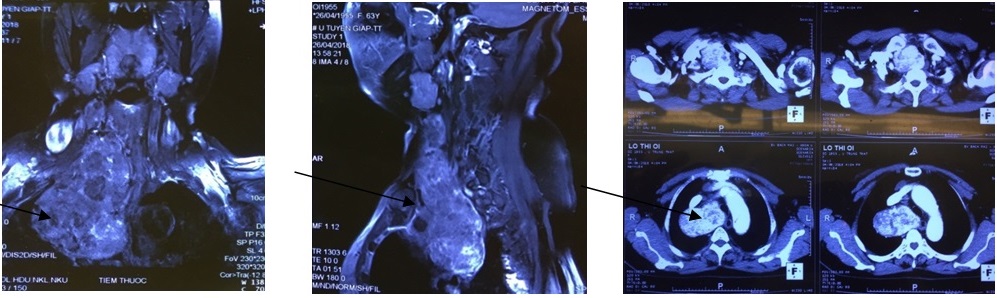

Triệu chứng ngày càng nặng, bệnh nhân đi khám ở bệnh viện tỉnh mới phát hiện ra một khối u lớn đã có dấu hiệu chèn ép vào khí quản và thực quản. Bệnh nhân được chuyển tuyến lên Bệnh viện Bạch Mai. Kết quả chụp Cắt lớp vi tính và cộng hưởng từ thấy khối u kích thước lớn 10x80x50mm sa vào trung thất, đè đẩy toàn bộ khí quản sang bên đối diện gây ảnh hưởng nghiêm trọng đến chức năng hô hấp: Rối loạn thông khí hạn chế mức độ vừa đến nhiều – đó là kết quả đo chức năng hô hấp và sinh thiết khối u trước mổ thấy bướu giáp keo lành tính.

Hình ảnh khối u trên phim Cắt lớp vi tính và Cộng hưởng từ